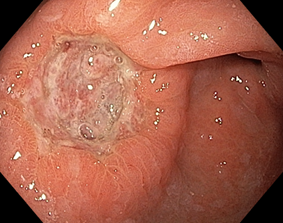

Эндоскопическая классификация стадий течения язвенного процесса по Sakita-Miwa

|

A1 |

H1

S1

A2

H2 |

S2 |

Рисунок 1. Стадии регрессии (заживления) язвы желудка и их характерные черты:

A (Active). Активная стадия (обострение)

A1. Слизистая оболочка, окружающая язву, выглядит набухшей в результате отёка, регенерация эпителия отсутствует.

A2. Отёк слизистой оболочки вокруг язвы уменьшился, край язвы отчётливо виден и в крае язвы появились первые ростки регенерирующего эпителия. По периметру язвы часто прослеживается красный ободок, а непосредственно по краю – циркулярный белый струп. Обычно, сходящиеся складки слизистой оболочки прослеживаются вплоть до края язвы.

H (Healing). Стадия заживления

H1. Слой белого фибрина, покрывающий язву, становится тонким, а регенерирующий эпителий распространяется непосредственно на основание язвы. Градиент между краем и дном язвы сглаживается. Но кратер язвы все еще очевиден, и край язвы отчётливо виден. Диаметр язвенного дефекта составляет примерно от половины до двух третей диаметра язвы в стадии A1.

H2. Язвенный дефект меньше, чем в стадии H1, и регенерирующий эпителий покрывает большую часть дна язвы. Площадь слоя белого фибрина составляет примерно от четверти до трети площади язвы в стадии А1.

S (Scarring). Стадия рубца

S1. Регенерирующий эпителий полностью покрывает дно язвы. Белый слой фибрина полностью исчез. Первоначально зона регенерации выглядит ярко красной. При прицельном осмотре можно увидеть большое количество капилляров. Сформировался "красный рубец".

S2. В срок от нескольких месяцев до нескольких лет исходно красный рубец принимает цвет окружающей слизистой оболочки. Сформировался «белый рубец».

Комментарий. Плановое эндоскопическое исследование подтверждает наличие язвенного дефекта, уточняет его локализацию, форму, размеры, глубину, состояние дна и краев язвы, позволяет выявить признаки пенетрации, рубцовой деформации и стенозирования просвета органа. Плановое эндоскопическое исследование дает возможность обнаружить другие сопутствующие изменения слизистой оболочки и определить нарушения гастродуоденальной моторики. Для оценки стадии язвенного процесса (обострение, заживление, рубцевание) целесообразно использовать общепринятую в мире классификацию Sakita-Miwa (рис.1).